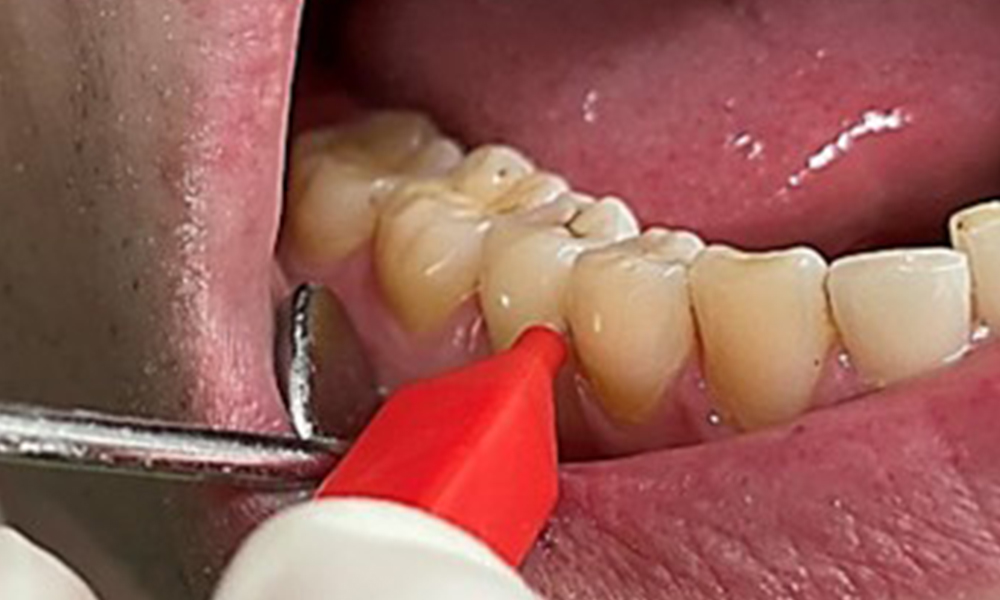

Biofilmul suplimentar poate fi îndepărtat cu ajutorul pudrelor cu glicină, mai slab abrazive. De reținut este că, după utilizarea unei pudre mai abrazive, este necesară și o etapă de finisare-lustruire (fig. 13).

Utilizarea unor paste de lustruire adecvate, cu conținut variat de ingrediente și cu valori RDA blânde corespunzătoare, va asigura netezirea și sigilarea eventualelor zone neuniforme de pe suprafața dintelui, fără a îndepărta extensiv substanța dentară.